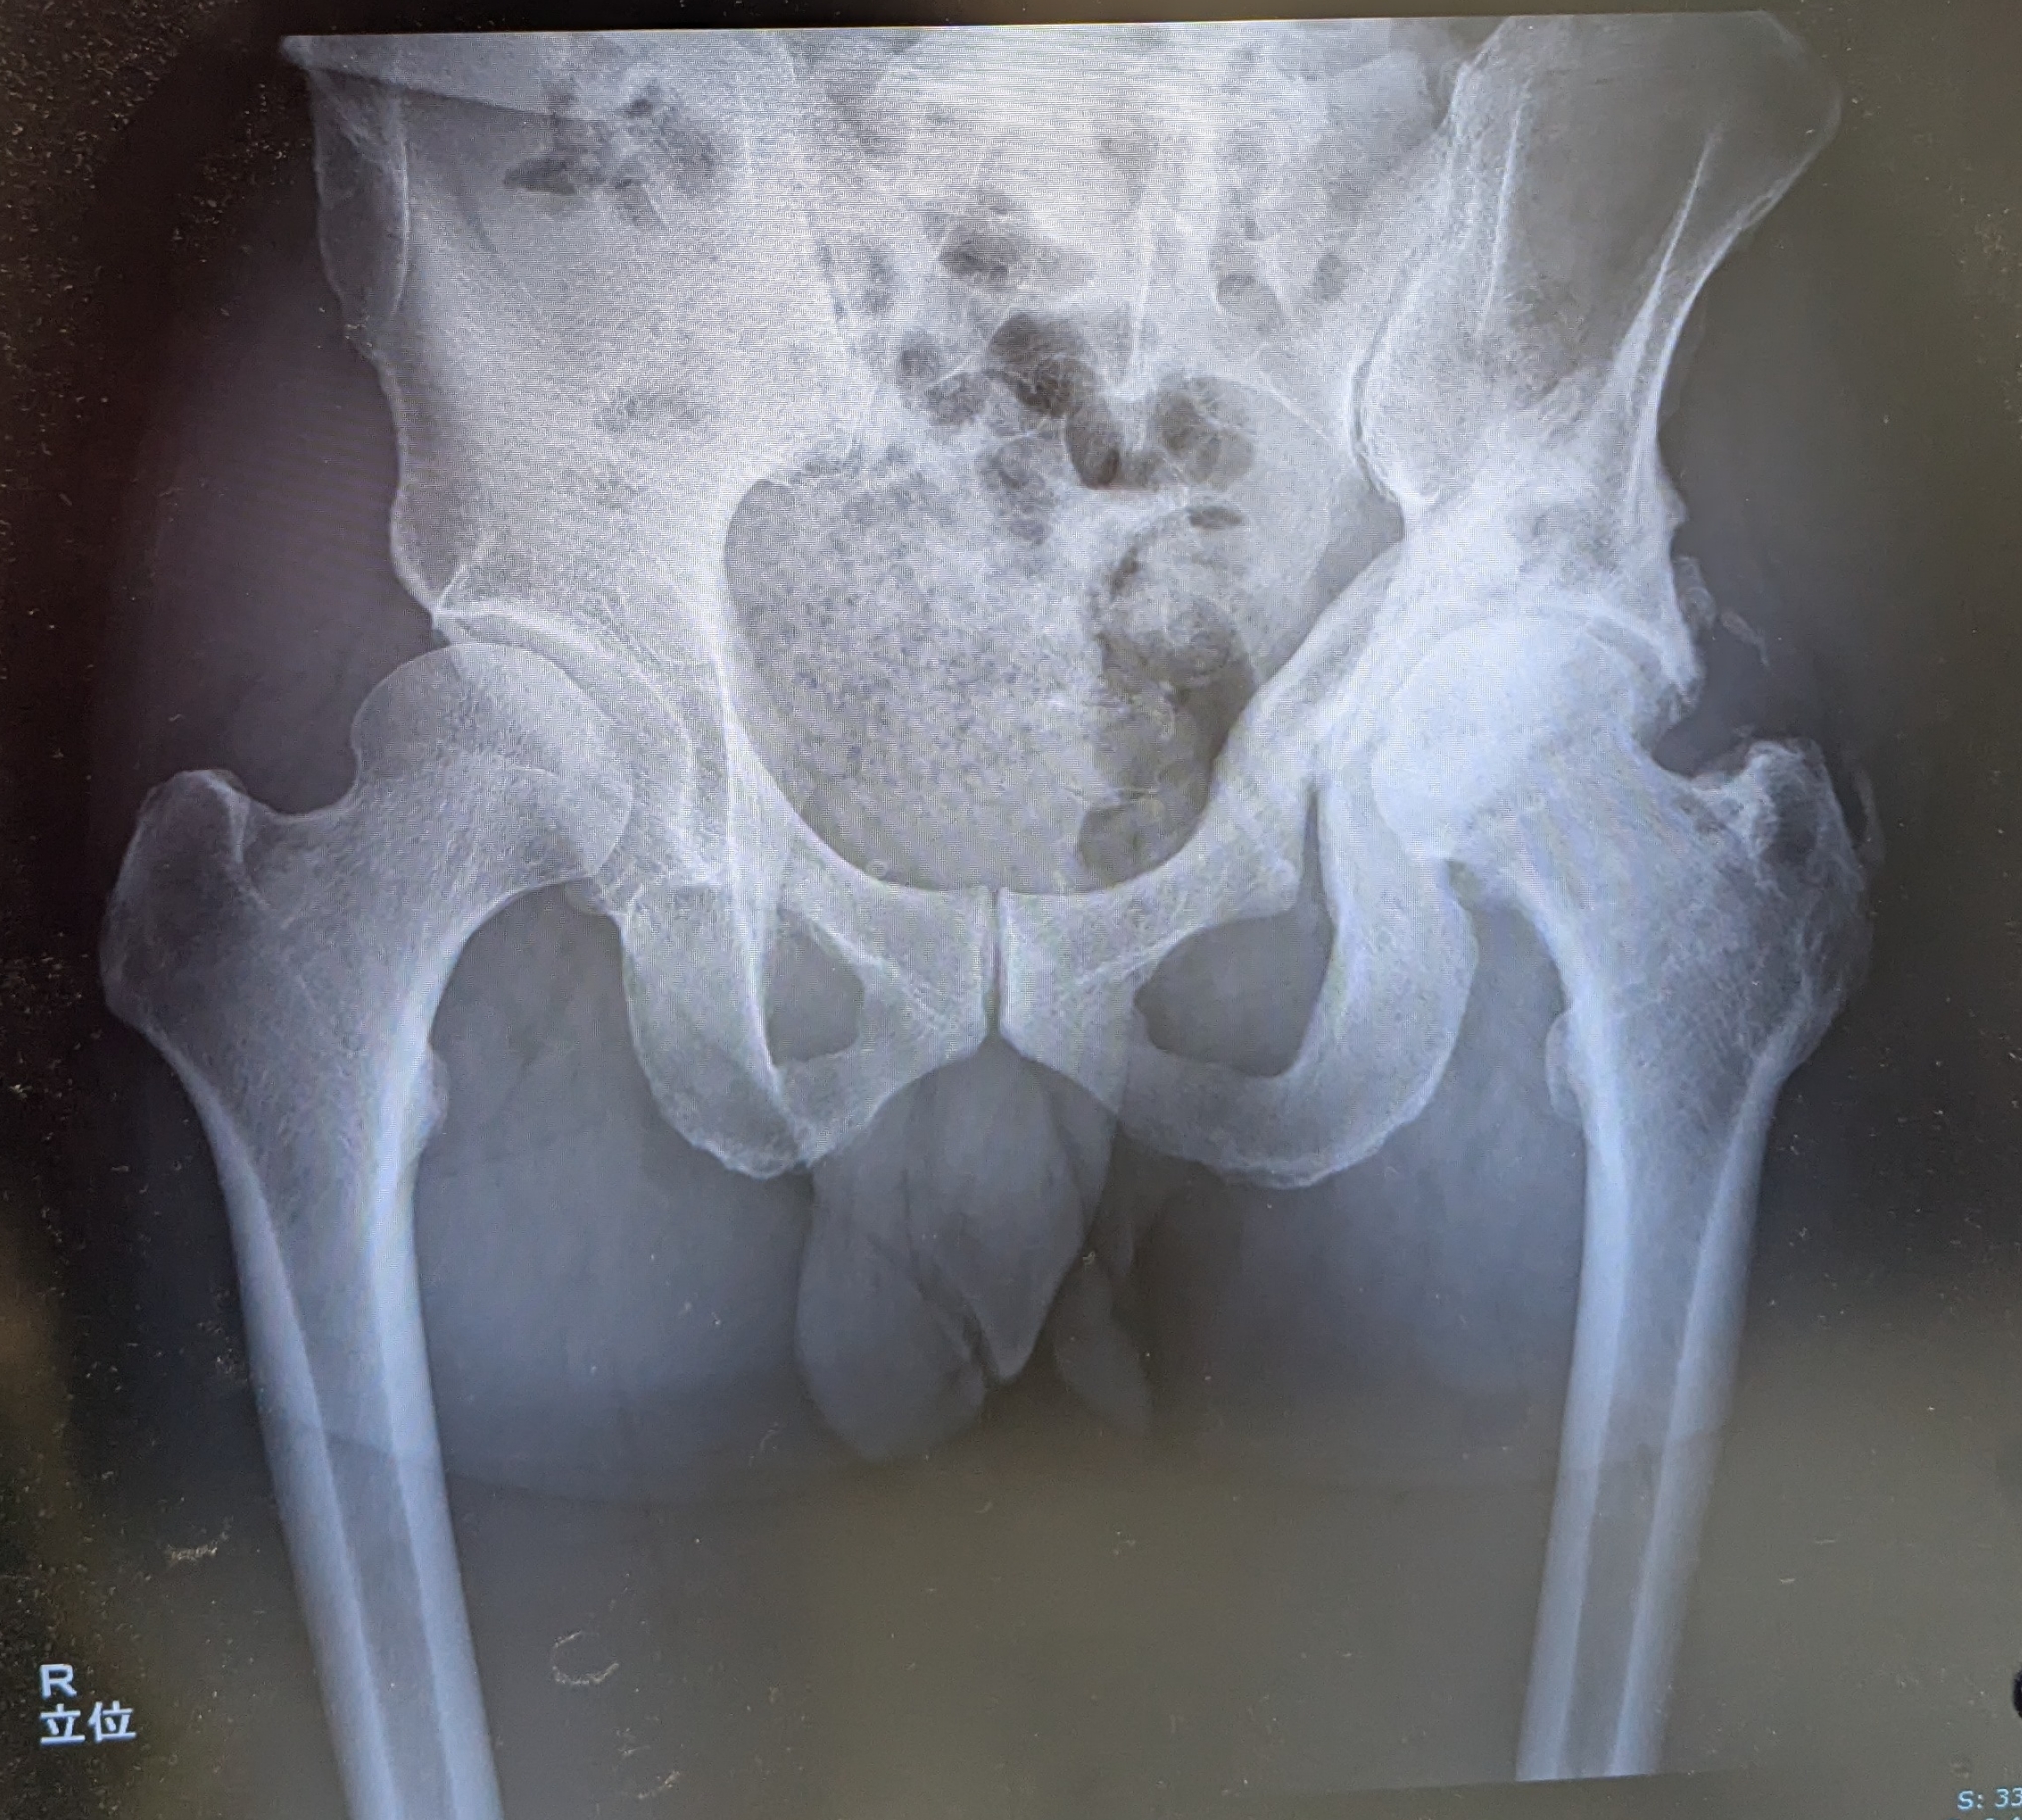

レントゲンは直ぐに呼ばれて、臥位と立位で合計3枚撮影。

はっきりいって芳しくない、、、。RAO手術から2年半。当初の目論見では、多少の可動域制限はあったとしても、もう痛みは全くないだろうって思ってたのに、相変わらず痛い。

- 異所性骨化巣の再発はなし